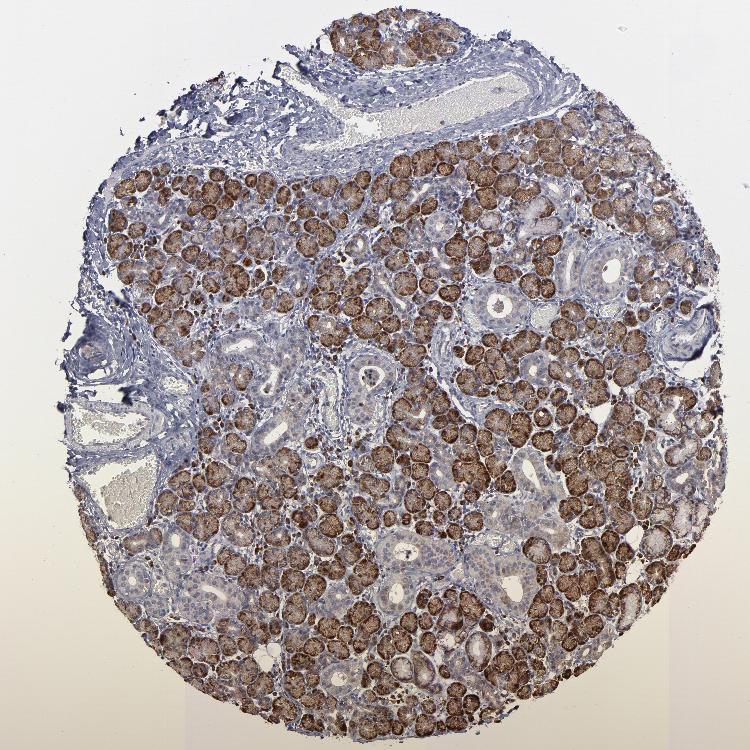

SALIVARY GLAND - Antibody stainingi

Antibody staining in the annotated cell types in the current human tissue is reported as not detected, low, medium, or high, based on conventional immunohistochemistry profiling in selected tissues. This score is based on the combination of the staining intensity and fraction of stained cells.

Each image is clickable and will lead to virtual microscopy that enables deeper exploration of all samples and also displays staining intensity scores, fraction scores and subcellular localization as well as patient and tissue information for each sample.

Antibody HPA002529Antibody HPA002632Antibody CAB019323

Glandular cells HighHighHigh